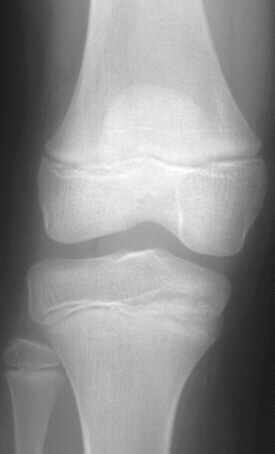

This 9 year old female presented to the emergency room with a four

day history of mild right knee pain. She limps on the affected extremity

when ambulating but has minimal to no pain at rest. No history of trauma

was reported. She has had mildly elevated temperatures over the past several

days according to the mother. There is no history of joint stiffness or

chronic fatigue. No other joints are involved. There is no history of tick

exposure. She has been otherwise healthy in the past. On physical examination

of the right knee there is no limitation in flexion or extension. There

is mild diffuse tenderness that is poorly localized over the medial femoral

condyle. There is no soft tissue swelling or joint effusion noted. No pain

is elicited with ROM of the knee. The remaining extremities are without

tenderness or swelling. Temperature is 38.8* C. LABS: WBC 13,400 Differential--

73% polys, 8% lymphs, 1% bands, Sed rate 41 mm/hr. The patient was discharged

home and re-checked the following day persistent tenderness over the knee

and new physical findings of swelling and pain with decreased Range Of

Motion of the knee, temperature was 39.2. She says she feels no different

than yesterday.